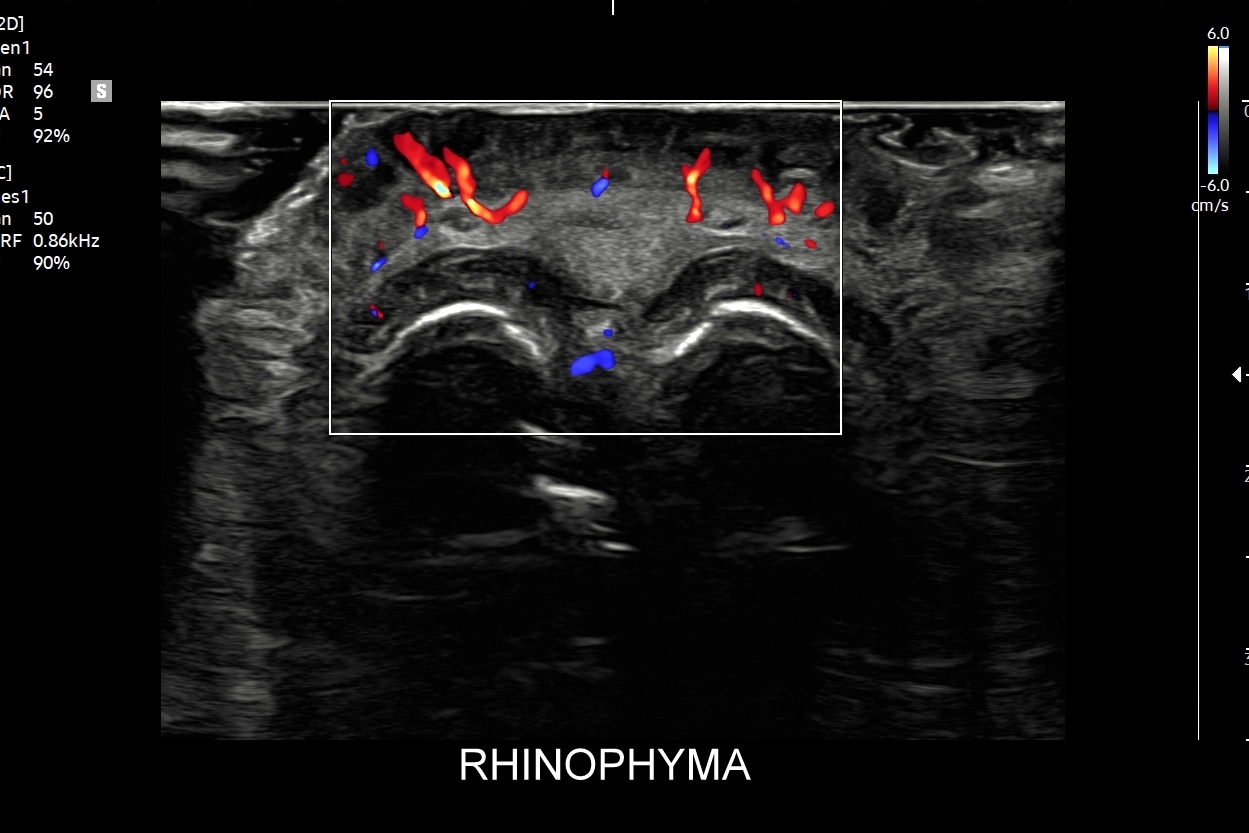

Badanie USG twarzy, często nie do końca fortunnie zwane USG skóry twarzy, to stosunkowo nowa metoda diagnostyczna wprowadzona we Wrocławiu do użytku przez dr Tomasza Szczepańskiego, a wykonywana w przypadku schorzeń z zakresu medycyny estetycznej, dermatologii, laryngologii, stomatologii i chirurgii. Wśród rozpoznań w badaniu USG skóry twarzy dominują choroby infekcyjne takie jak rozprzestrzeniające się w tkankach miękkich zapalenia i ropowice pochodzące od zapaleń zębów czy migdałków, powikłania ropne w przebiegu trądziku pospolitego lub różowatego, po iniekcjach wypełniaczy i po innych zabiegach z zakresu medycyny estetycznej. Kolejną dużą grupą patologii skóry twarzy są torbiele inkluzyjne, których przykładem są kaszaki, oraz guzy twarzy, wśród których dominują ziarniniaki jako odległe acz częste powikłanie depozycji wypełniaczy z kwasu hialuronowego.

USG twarzy wykorzystywane jest także do diagnozowania urazów twarzoczaszki, zarówno w obrębie tkanek miękkich (np. uraz zmiażdżeniowy tkanki podskórnej), jak i kości (np. złamanie kości jarzmowej, kości nosa); do oceny zaawansowania bruksizmu; oceny i kategoryzowania naczyniaków twarzoczaszki; diagnozowania zapaleń tętnic skroniowych; czy powikłań naczyniowych w medycynie estetycznej. Badanie USG twarzy służy również do oceny defektów kosmetycznych zarówno przed ewentualnymi zabiegami estetycznymi i plastycznymi, jak i po nich.